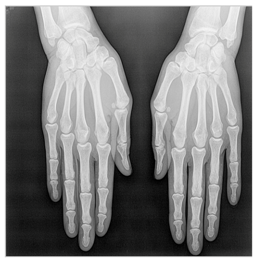

In this section, we present and analyze the results obtained with the proposed method, and compare it to methods proposed in similar works. The proposed watermarking system is implemented using MATLAB and executed on a Windows machine with the following characteristics: Intel R Core i5 processor, 4 GHz, 4 GB RAM, and Microsoft Windows 8 Professional operating system platform. In our experiments, we have used DICOM images of size 512 × 512 pixels as shown in Table 1.

Table 1.

Original images.